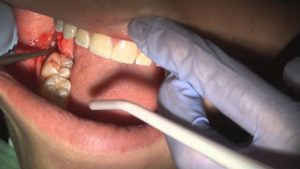

Viêm ổ răng là biến chứng thông thường sau khi nhổ răng. Bệnh nhân đau cực kỳ dữ dội, khám hốc răng thấy trống hoặc có cục máu đông nhưng lấy ra dễ dàng, để trơ những thàng xương hơi trắng và không có màu, không có mủ, mùi hơi khó chịu.

Bệnh nhân đau cực kỳ dữ dội, khám hốc răng thấy trống hoặc có cục máu đông nhưng lấy ra dễ dàng, để trơ những thàng xương hơi trắng và không có màu, không có mủ, mùi hơi khó chịu.

Chứng viêm này xảy ra một vài ngày sau khi nhổ răng và tình trạng kéo dài 2-3 tuần lễ, bệnh nhân đau đớn không làm việc được. Viêm có mủ thấy bờ lợi sưng có thể che phủ ổ răng, và nó được lấp bởi những nụ tổ chức hạt rớm máu và có mủ chảy ra.

Với viêm ổ răng có mủ cần: gây tê vùng , nạo sạch ổ răng, lấy hết vật còn sót, rửa sạch và đặt thuốc để chống nhiễm khuẩn. Trường hợp nặng sẽ phải bổ sung kháng sinh, giảm đau.